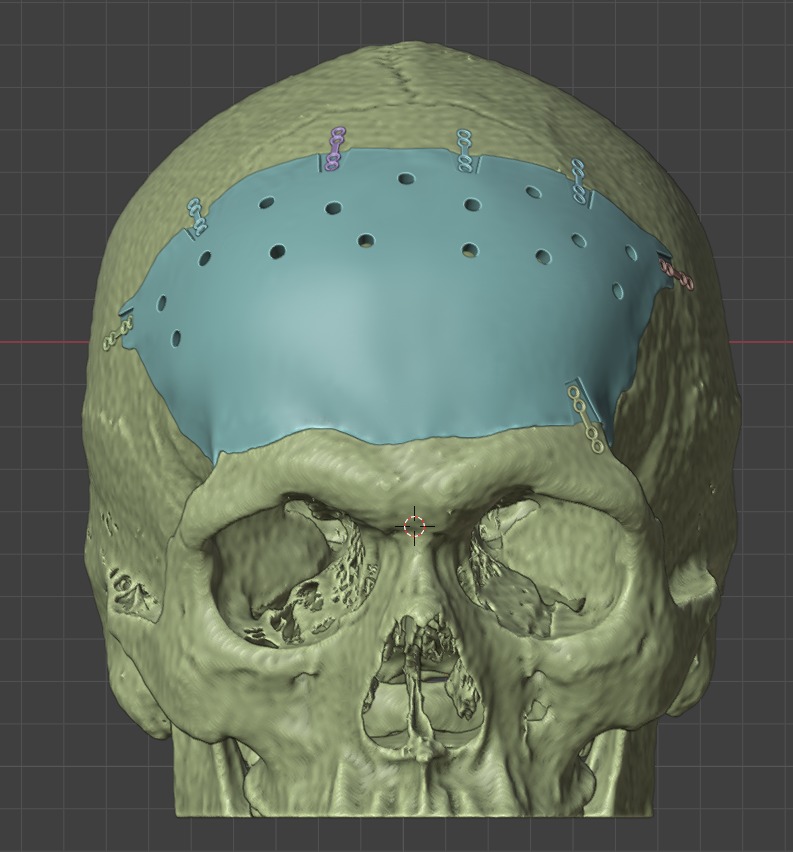

El diseño personalizado de los implantes permite ajustarse a las necesidades

de cada paciente y cirujano mediante la selección de diferentes características

de diseño.

Cada implante se fabrica adaptado a la anatomía específica de cada paciente,

reduciendo el tiempo de ajuste del mismo durante la cirugía.

La información necesaria para el diseño personalizado se obtiene a partir de la

Tomografía Axial Computada (TAC) del paciente.

Captura y Modelado 3D

La reconstrucción anatómica se realiza a partir de imágenes obtenidas mediante técnicas de diagnóstico como Tomografía Axial Computada (TAC) o Resonancia Magnética (MRI). Estas imágenes son procesadas con software especializado para modelar en tres dimensiones cualquier región anatómica, incluso con patologías complejas.

Inclusión de Implantes

En el modelado digital 3D se pueden incluir implantes ortopédicos como placas, tornillos, mallas, prótesis y otros dispositivos, diseñados en tamaño real y en relación directa con la anatomía del paciente. Esto permite simular distintos escenarios quirúrgicos antes de la cirugía.